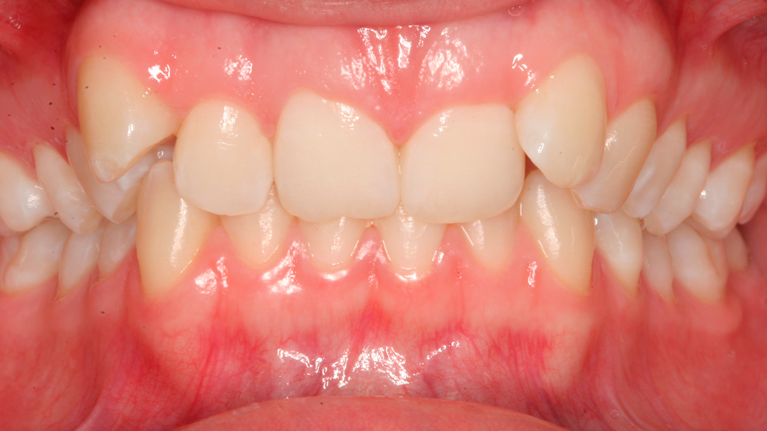

Til konferencen møder du en kirurgisk specialtandlæge fra Kæbekirurgisk Afdeling, muligvis en uddannelsestandlæge og en bøjletandlæge. De fremlægger den foreløbige behandlingsplan, som de forinden har udarbejdet. Du har mulighed for at få uddybet eventuelle spørgsmål til behandlingsplanen.